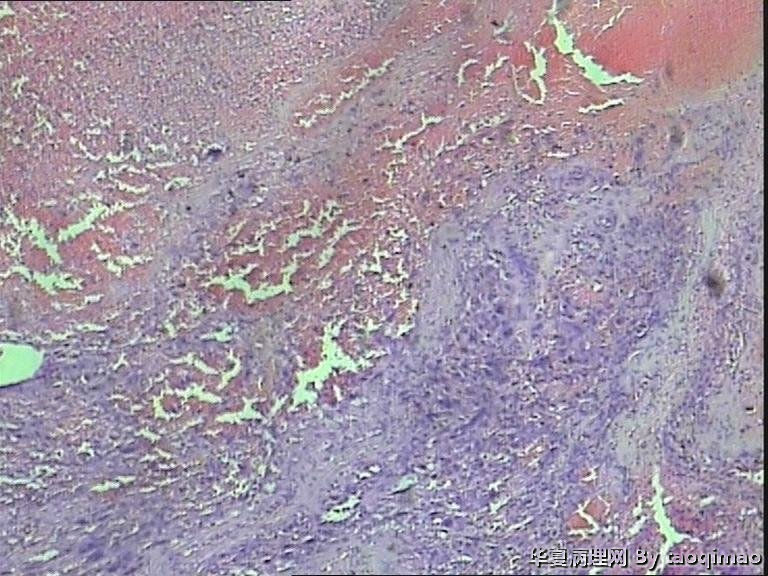

• 功血,滋养细胞浅肌层?图3

图3

上一组图是全子宫切除后宫内膜及浅肌层的切片,取材时发现在子底及后壁有暗紫色血凝块与宫内膜分界不清

追问病史 除外绒癌 侵袭性葡萄胎